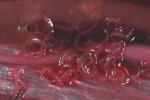

Ողբերգական վթար Իջևան-Երևան ավտոճանապարհին. վարորդը տեղում մահացել է, կան վիրավորներ Վանաձորում 36-ամյա տղամարդու սպանության մեջ կասկածվող անձը ձերբակալվել է Կարեն Կարապետյանը՝ զույգ թոռների պապիկ. ծնվել են փոխնախարար Հայկ Հարությունյանի երեխաները Հայրիկյանի հացադուլը ԿԸՀ դիմաց (տեսանյութ) 19-ամյա աղջիկը կամրջից իրեն ցած է նետել Երևանում 23-ամյա վարորդը «Honda» մոպեդով վրաերթի է ենթարկել Արաբկիր համայնքի համատիրության 22-ամյա աշխատակցուհուն. ՖՈՏՈՌԵՊՈՐՏԱԺ Ստեփանծմինդա-Լարս ավտոճանապարհի վիճակի մասին Վանաձորում համաձայնությունը կայացավ. ՀՎԿ-ն համագործակցության հուշագիր է կնքել ՀՀԿ-ի հետ Ադրբեջանցի 20 դիպուկահար մարզվում է Թուրքիայի ոստիկանությունում (տեսանյութ) Լավրովը հանդիպել է Ալիևին, փոխանցել Պուտինի ջերմ բարևները Երևանում 41-ամյա վարորդը Range Rover-ով բախվել է կայանված ավտոմեքենաներին, նրանցից մեկն էլ վրաերթի է ենթարկել հետիոտնին Արաբկիր համայնքի համատիրության 22-ամյա աշխատակցուհին վթարի է ենթարկվել Լավրովը պաշտոնական այցով գտնվում է Բաքվում Արցախում նախրապանը ականի վրա է կանգնել, որը պայթել է Ձերբակալվել է փաստաբան Հյուսիսային Կորեայից փախած զինվորի մարմնից սարսափելի մակաբույծներ են հեռացնում Սեպտեմբերին Թուրքիայի արտաքին պարտքը կազմել է 665.5 մլրդ դոլար.ermenihaber.am Ուսանողների հանրային քննարկումը՝ կլոր սեղանին ընդառաջ. ուղիղ Պետդեպը հրապարակել է ոչ միգրացիոն վիզաների հարցում մերժման վիճակագրությունը Ավտովթար Արագածոտնի մարզում Արտակարգ դեպք Երևանում. ահազանգ է ստացվել, որ Մետրոպոլիտենի տարածքում զինված քաղաքացի կա Տղամարդուն փրկել են «Քվանտ» վարժարանի 2 սաները Նախարարներից ովքե՞ր են անցել պարտադիր զինվորական ծառայություն Սպանություն՝ Վանաձորում. Ձեռնարկված անհետաձգելի գործողությունների արդյունքում կասկածյալի ինքնությունը պարզվել է Արտակարգ դեպք Երևանում. 13-ամյա տղան դանակի հարվածով տեղափոխվել է «Սբ. Գրիգոր Լուսավորիչ» բժշկական կենտրոն Փրփրակալած երախներով այդ նույն զինված ուժերը քայքայող կոռուպցիայի դեմ խոսողների՞ն եք ուզում լռեցնել Եթե մոռանանք, դա հաստատ կկրկնվի. Աննա Աստվածատուրյան-Տերկոտ Սամվել Կարապետյանը` «Արարատ» ՖԱ նախագահ Կաթիլային ընդունող ժողովուրդը կարող է և մեռնել, որպեսզի ՀՀԿ-ի ռեինկարնացիան շարունակական լինի Էրդողանը պատմել է, թե ինչ է խոսել Պուտինի հետ Ղարաբաղի խնդրի վերաբերյալ